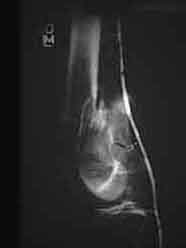

An initial injury film shows a closed supracondylar femur fracture with an arteriogram done for questionable signs of arterial injury showing a nonocclusive intimal flap of the popliteal artery. Since this arterial injury fit the published criteria for nonop observation, our orthopedic surgeons went ahead and did ORIF. 6 weeks later a F/U angio shows complete resolution of the intimal flap -- unnecessary surgery thus avoided.

This illustrates the RULE for nonocclusive arterial injuries, NOT the exception.

6 weeks later

can you make a better image? The resolution is inadequate to assess the images. All I see is luminal narrowing, consistent with vasospasm.

I'll try--there is an intraluminal defect consistent with a flap.

Click to zoom in on these images:

Injury

with regard to this image i imagine i see what eric is talking about but still think that this could be spasm. Eric any other views?